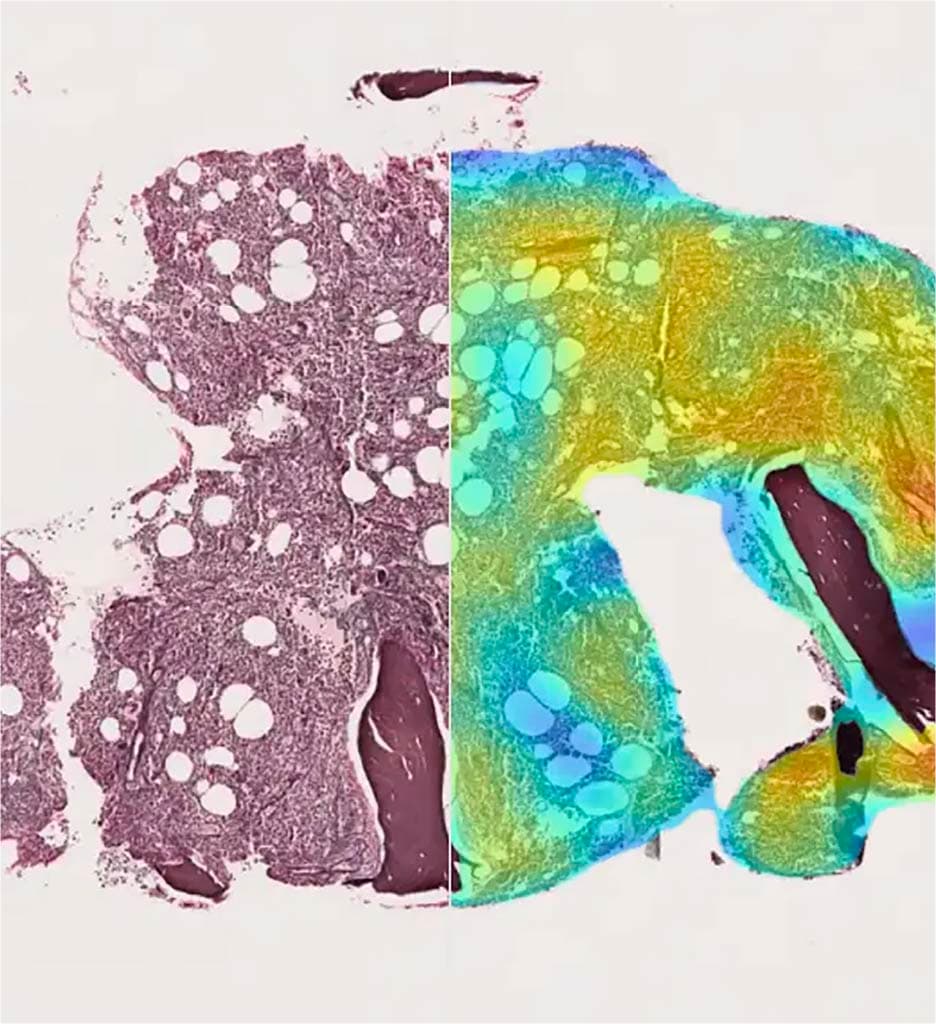

AI, big data and research tools that accelerate discovery, reduce costs, and bring new therapies to patients faster.

From AI-powered diagnostics to digital surgery, our companies are reimagining care, accelerating research, and advancing global health.